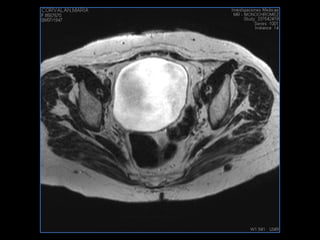

PROTOCOLO pelvis SAG T2, Y FAT SAT (FINOS) AXIAL T1  AX FAT SAT CON   GADOLINIO :  AX T1 Y COR T1 SAT: NO  FASE: RL THK: 3MM  COIL:  GAP: (FACTOR 1.4) 1MM FOV: 40 CM NEX:2 SINCRONIZACION RESPIRATORIA EN 3 O 4 CICLOS ALE